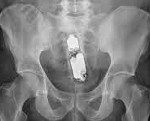

T18.5 Инородное тело в заднем проходе и прямой кишке